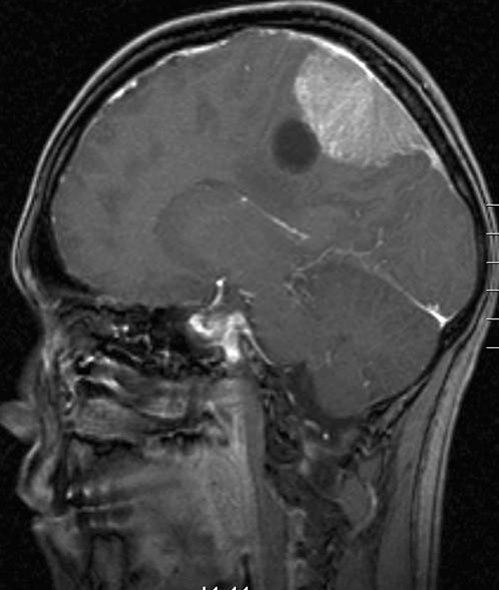

Meningeom med cyste, sagittalt snitt

Gjengitt med tillatelse av Radiologisk avdeling, Universitetssykehuset Nord-Norge